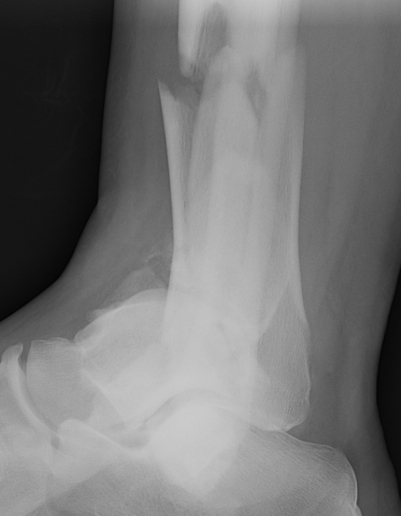

Severe Tibial PlafondAnterolateral fragment and valgus injuryTibial Plafond External Fixator

Tibial Plafond Pre External Fixator APTibial Plafond Pre External Fixator LateralTibial Plafond Post External Fixator APTibial Plafond Post External Fixator Lateral